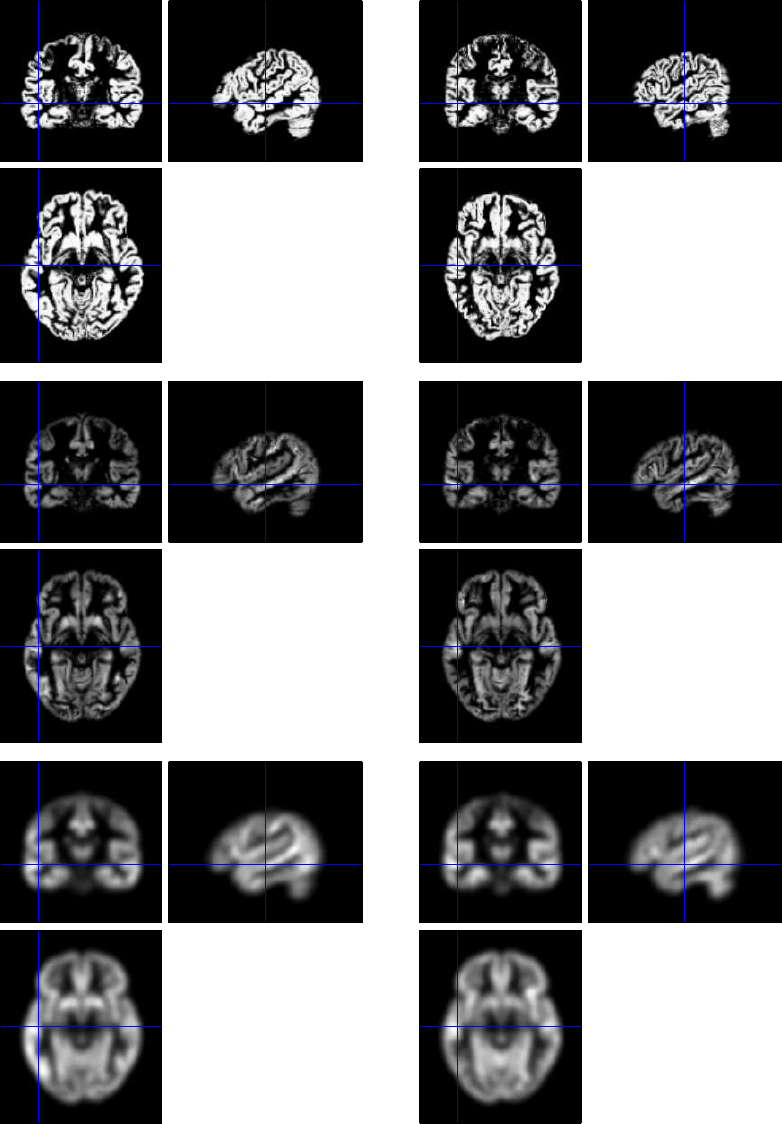

42.7.2 Normalisation/Segmentation of T1 images ...................422

42.7.3 Coregistration of mean EPI (fMRI) to T1 (sMRI) ..............422

42.7.4 Application of Normalisation parameters to EPI data ............422

42.7.5 Smoothing ....................................423

42.7.6 Creating a 1st-level (fMRI) GLM ........................423

42.7.7 Model Estimation ................................423

42.7.8 Setting up contrasts ...............................423

42.7.9 Group Statistics on fMRI data .........................425

42.8 Source Reconstruction ..................................425

42.8.1 Create Head Model ................................427

42.8.2 Model Inversion .................................428

42.8.3 Time-frequency contrasts ............................428

42.8.4 Group Statistics on Source Reconstructions ..................431

42.9 Group Source Reconstruction ..............................433

42.9.1 Group Statistics on Source Reconstructions ..................433

42.10Group MEEG Source Reconstruction with fMRI priors ................433

42.10.1 Group Statistics on Source Reconstructions ..................435